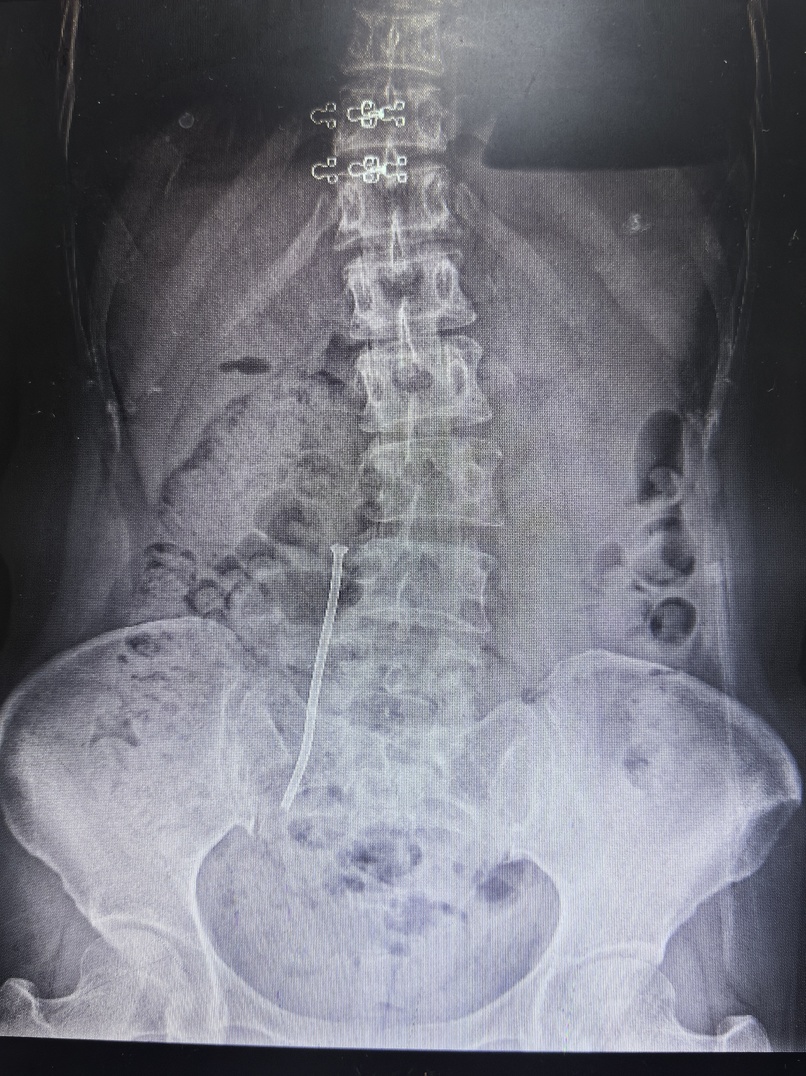

微信圖片_20241122082919.jpg

術(shù)后復(fù)查X片支架在位